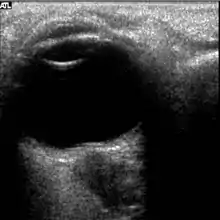

The first U.S. case of visual changes observed on orbit was reported by a long-duration astronaut that noticed a marked decrease in near-visual acuity throughout his mission on board the ISS, but at no time reported headaches, transient visual obscurations, pulsatile tinnitus or diplopia (double vision). His postflight fundus examination (Figure 1) revealed choroidal folds below the optic disc and a single cotton-wool spot in the inferior arcade of the right eye. The acquired choroidal folds gradually improved, but were still present 3 year postflight. The left eye examination was normal. There was no documented evidence of optic-disc edema in either eye. Brain MRI, lumbar puncture, and OCT were not performed preflight or postflight on this astronaut.[5]